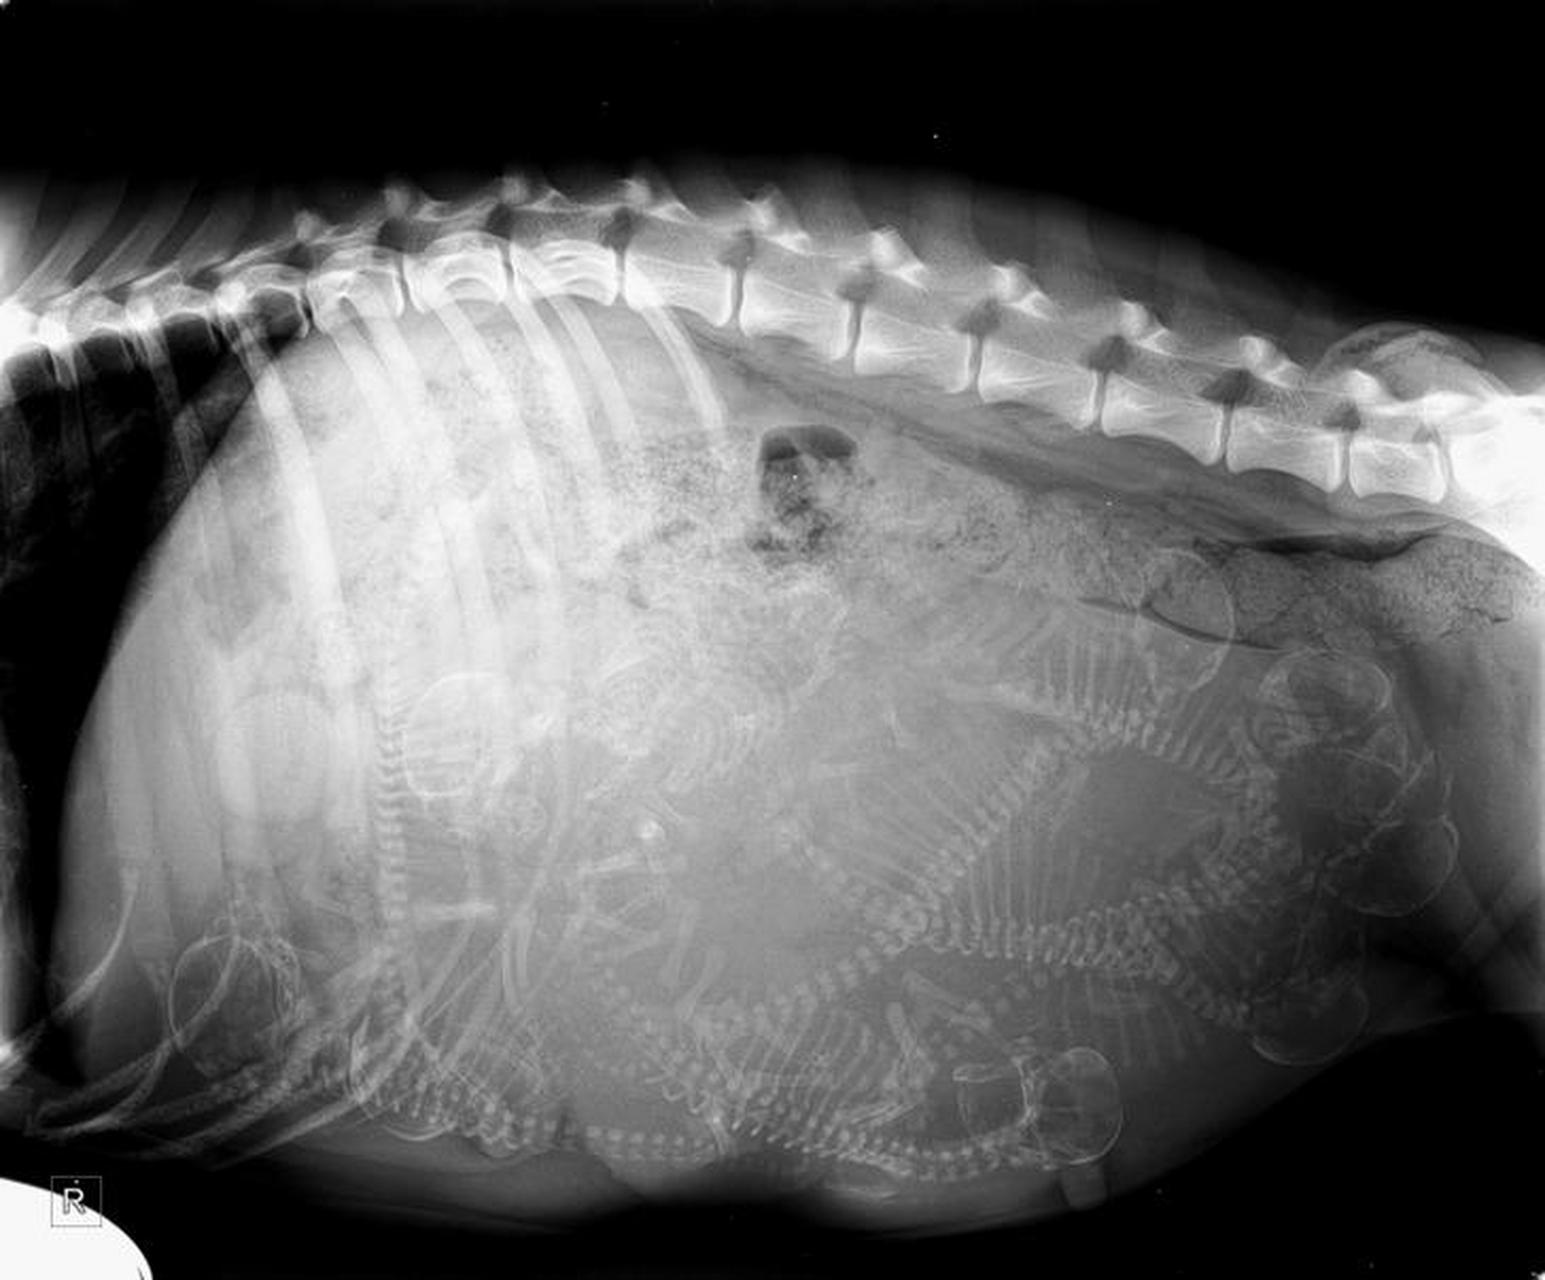

怀孕的狗的x光片,大家数数肚子里有几只狗宝宝#动态创作月

怀孕狗狗的x光照片.